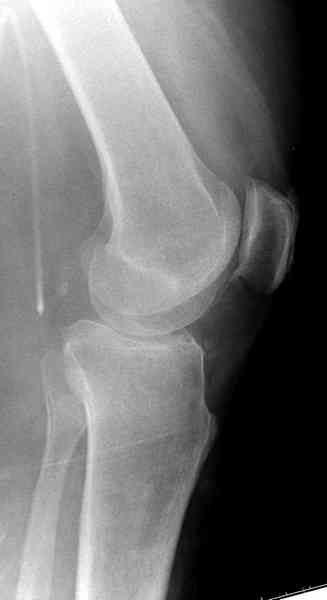

Здравствуйте, уважаемые коллеги!Подскажите, пожалуйста, какой выбрать доступ и способ фиксации при импрессионном переломе заднего отдела наружного мыщелка большеберцовой кости. Женщина 40 лет, травму получила 02.01.2008, катаясь на горных лыжах.Есть ли здесь необходимость использовать задний доступ, или можно справиться через наружный? Есть ли шансы сделать закрыто - под ЭОП через медиальное "окошко" поднять забойником суставную поврехность? Какой лучше использовать фиксатор?Спасибо.

Из медиального окна можно приподнять латеральную

импрессию. Фиксация тремя параллельными шурупами в

эпифизарной части над импрессией. Создается крыша,

которая предупредит коллапс. На образовавшуюся полость - костная пластика из аутокости или синтетический заменитель. Мы применяем Osteoset в 4-5 мм диаметре таблеточки или иньекционную форму Prodens.

Медиально, обычно на протовоположной

строне, делается окно в кортикальном слое, кривым забойником под рентгеном поднимается импрессия.

Это техника применяется, когда имеется

центральная импрессия, а при ипрессии с краевым переломом - после приподнимания импрессии опорная (Butress) пластина, как на снимке.